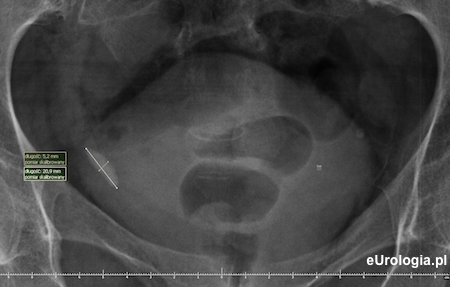

Urografia - duży złóg w dolnym odcinku prawego moczowodu

Zdjęcie przeglądowe nerek i pęcherza - cień wpaienny w miednicy po stronie prawej o wymiarach 20x10 mm

Zdjęcie wykonane godzinę po mikcji - zakontrastowany mocz w pęcherzu moczowym. Cień wapienny 20x10 mm będący złogiem w dolnym odcinku prawego moczowodu.

Kamień w dolnym odcinku prawego moczowodu - cień wapienny w miednicy małej widoczny na zdjęciu przeglądowym nerek i pęcherza.